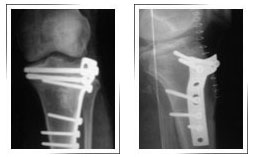

Fracture Tibial Plateau with metaphyseal extension :

After Surgery